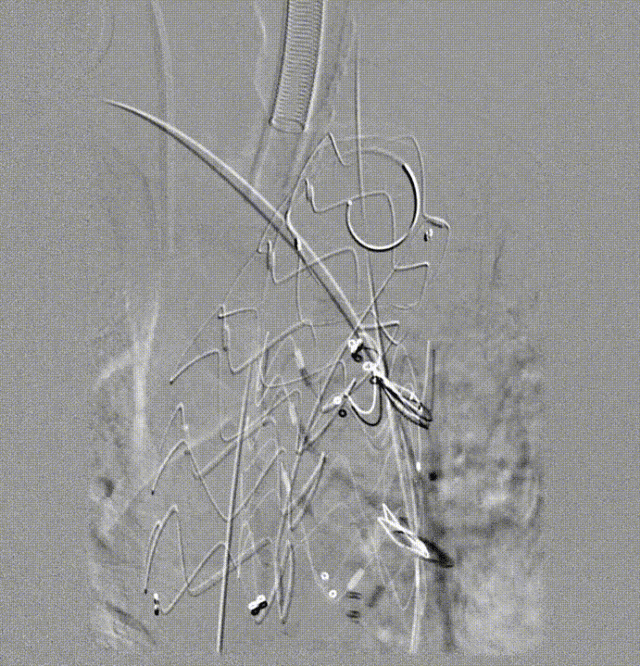

② 分支重建

通过右侧肱动脉进入头臂干,经左侧颈动脉选择性进入另一内嵌分支

用12/40球囊同时扩张,证实导丝在分支内

重建头臂干。造影找到合适角度,使右颈总和右锁骨下动脉分开,定位,植入18-13-120mm支架,之后球囊扩张。造影显示血流良好。

重建左颈总动脉。植入10-13-120mm支架,植入后球囊扩张,血流同样良好。

③ 跨弓主动脉支架植入

支架型号:WFS-RS-42-38-200mm,近端直径42mm,远端38mm,长度20cm。

该支架具有可调弯特性,体外旋转使Tip头下压后进行跨弓操作,可以避免输送器对已植入分支支架造成移位。

经左侧桡动脉植入导管,造影标记左锁骨下动脉开口位置,使跨弓支架的左锁骨下动脉内嵌分支开口 Mark 点对LSA开口。

通过内嵌逆向分支进入左锁骨下动脉,利用导丝牵张技术建立轨道,经股动脉植入左锁骨下动脉分支支架18-11-60mm(输送器 12F)。